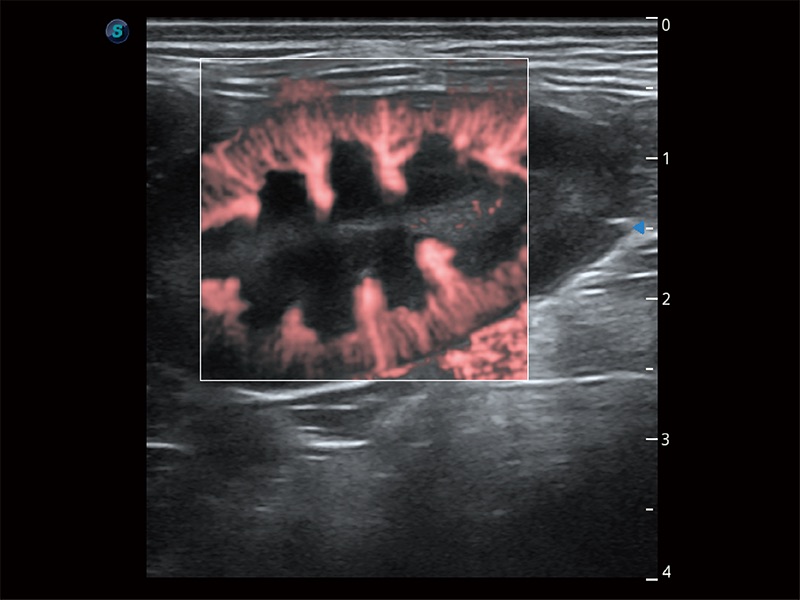

高性能和先进的临床应用工具可以为动物医生提供临床信心。ProPet 80 搭载了先进的腹部和浅表应用工具,帮助医生在日常临床实践中发挥前所未有的作用。

操作简便,无需高频度外力作用即可真实反映组织的形变,快速评估肿瘤良恶性。

为精细结构及组织边缘提供高清晰度的图像和更大的成像视野。帮助减轻医生的用眼疲劳,快速精准获得测量的数据。